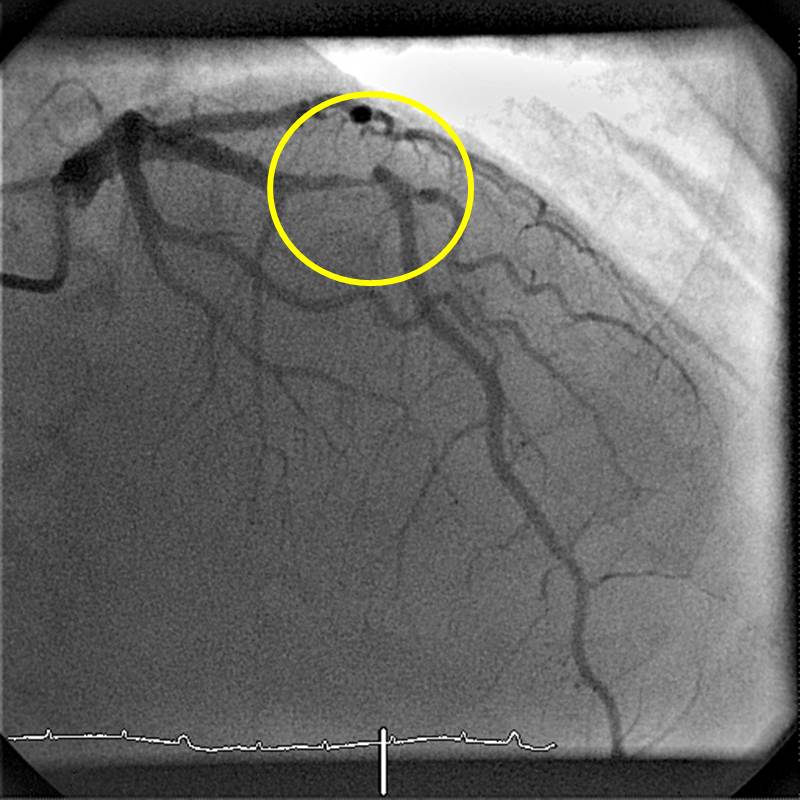

RIVA vor Stent

Hochgradige Stenose der Vorderwandherzkranzarterie (Markierung durch gelben Kreis)

RIVA nach Stent

Darstellung der Vorderwandherzkranzarterie nach Stentimplantation. Die Stenose ist nicht mehr nachweisbar (Markierung durch gelben Kreis).